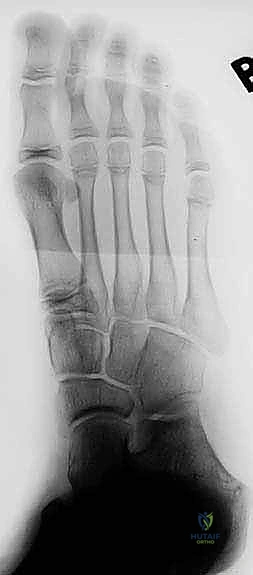

- الأشعة السينية التقليدية (X-Rays): يتم أخذ صور بوضعيات خاصة (مثل وضعية Harris-Beath) لرؤية المفصل تحت الكاحل. قد تظهر الأشعة السينية الائتلاف العظمي بوضوح، بالإضافة إلى علامات ثانوية مثل "علامة حرف C" (C-sign) التي تدل على تشوه في عظم الكاحل، أو وجود نتوءات عظمية (Osteophytes) تشير إلى بداية خشونة المفاصل المجاورة.

- التصوير المقطعي المحوسب (CT Scan): يُعد المعيار الذهبي (Gold Standard) لتشخيص ائتلاف الكاحل العقبي. يطلب الدكتور هطيف إجراء أشعة مقطعية ثلاثية الأبعاد، حيث توفر صوراً متناهية الدقة للتركيب العظمي، تحدد حجم الائتلاف، موقعه الدقيق، ونسبة إصابة المفصل. هذه الخطوة حاسمة جداً قبل اتخاذ قرار الجراحة.